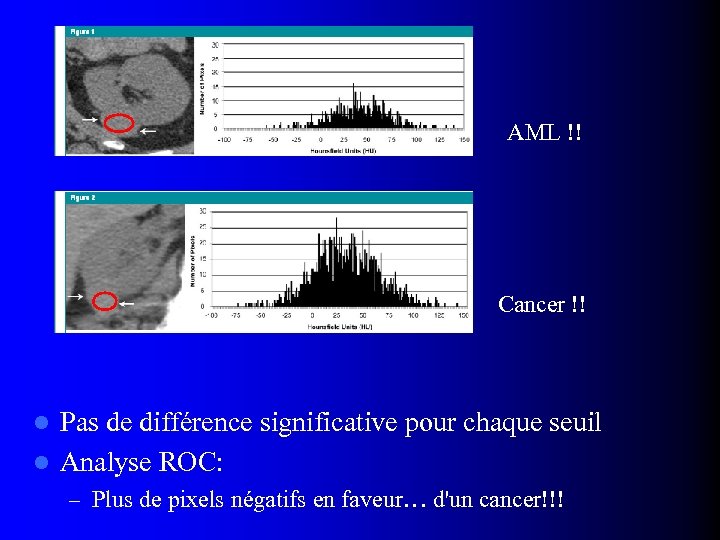

TDM: Analyse de la densité individuelle des pixels l Catalano OA et al, Radiology 2008; 247: 738 – 22 AMLs sans graisse prouvés histologiquement – Coupes sans injection – ROI: au moins ¾ de la plus grande surface – Histogrammes : distribution de la densité des pixels – Pourcentage de pixels en dessous d'un certain seuil (-20 UH à +10 UH)

TDM: Analyse de la densité individuelle des pixels l Catalano OA et al, Radiology 2008; 247: 738 – 22 AMLs sans graisse prouvés histologiquement – Coupes sans injection – ROI: au moins ¾ de la plus grande surface – Histogrammes : distribution de la densité des pixels – Pourcentage de pixels en dessous d'un certain seuil (-20 UH à +10 UH)

AML !! Cancer !! Pas de différence significative pour chaque seuil l Analyse ROC: l – Plus de pixels négatifs en faveur… d'un cancer!!!

AML !! Cancer !! Pas de différence significative pour chaque seuil l Analyse ROC: l – Plus de pixels négatifs en faveur… d'un cancer!!!